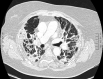

Association between Hydroxychloroquine (HCQ) and Azithromycin (AZT) is under evaluation for patients with lower respiratory tract infection (LRTI) caused by the Severe Acute Respiratory Syndrome (SARS-CoV-2). Both drugs have a known torsadogenic potential, but sparse data are available concerning QT prolongation induced by this association. Our objective was to assess for COVID-19 LRTI variations of QT interval under HCQ/AZT in patients hospitalized, and to compare manual versus automated QT measurements. Before therapy initiation, a baseline 12 lead-ECG was electronically sent to our cardiology department for automated and manual QT analysis (Bazett and Fridericia's correction), repeated 2 days after initiation. According to our institutional protocol (Pasteur University Hospital), HCQ/AZT was initiated only if baseline QTc ≤ 480ms and potassium level> 4.0 mmol/L. From March 24th to April 20th 2020, 73 patients were included (mean age 62 ± 14 years, male 67%). Two patients out of 73 (2.7%) were not eligible for drug initiation (QTc ≥ 500 ms). Baseline average automated QTc was 415 ± 29 ms and lengthened to 438 ± 40 ms after 48 hours of combined therapy. The treatment had to be stopped because of significant QTc prolongation in two out of 71 patients (2.8%). No drug-induced life-threatening arrhythmia, nor death was observed. Automated QTc measurements revealed accurate in comparison with manual QTc measurements. In this specific population of inpatients with COVID-19 LRTI, HCQ/AZT could not be initiated or had to be interrupted in less than 6% of the cases.